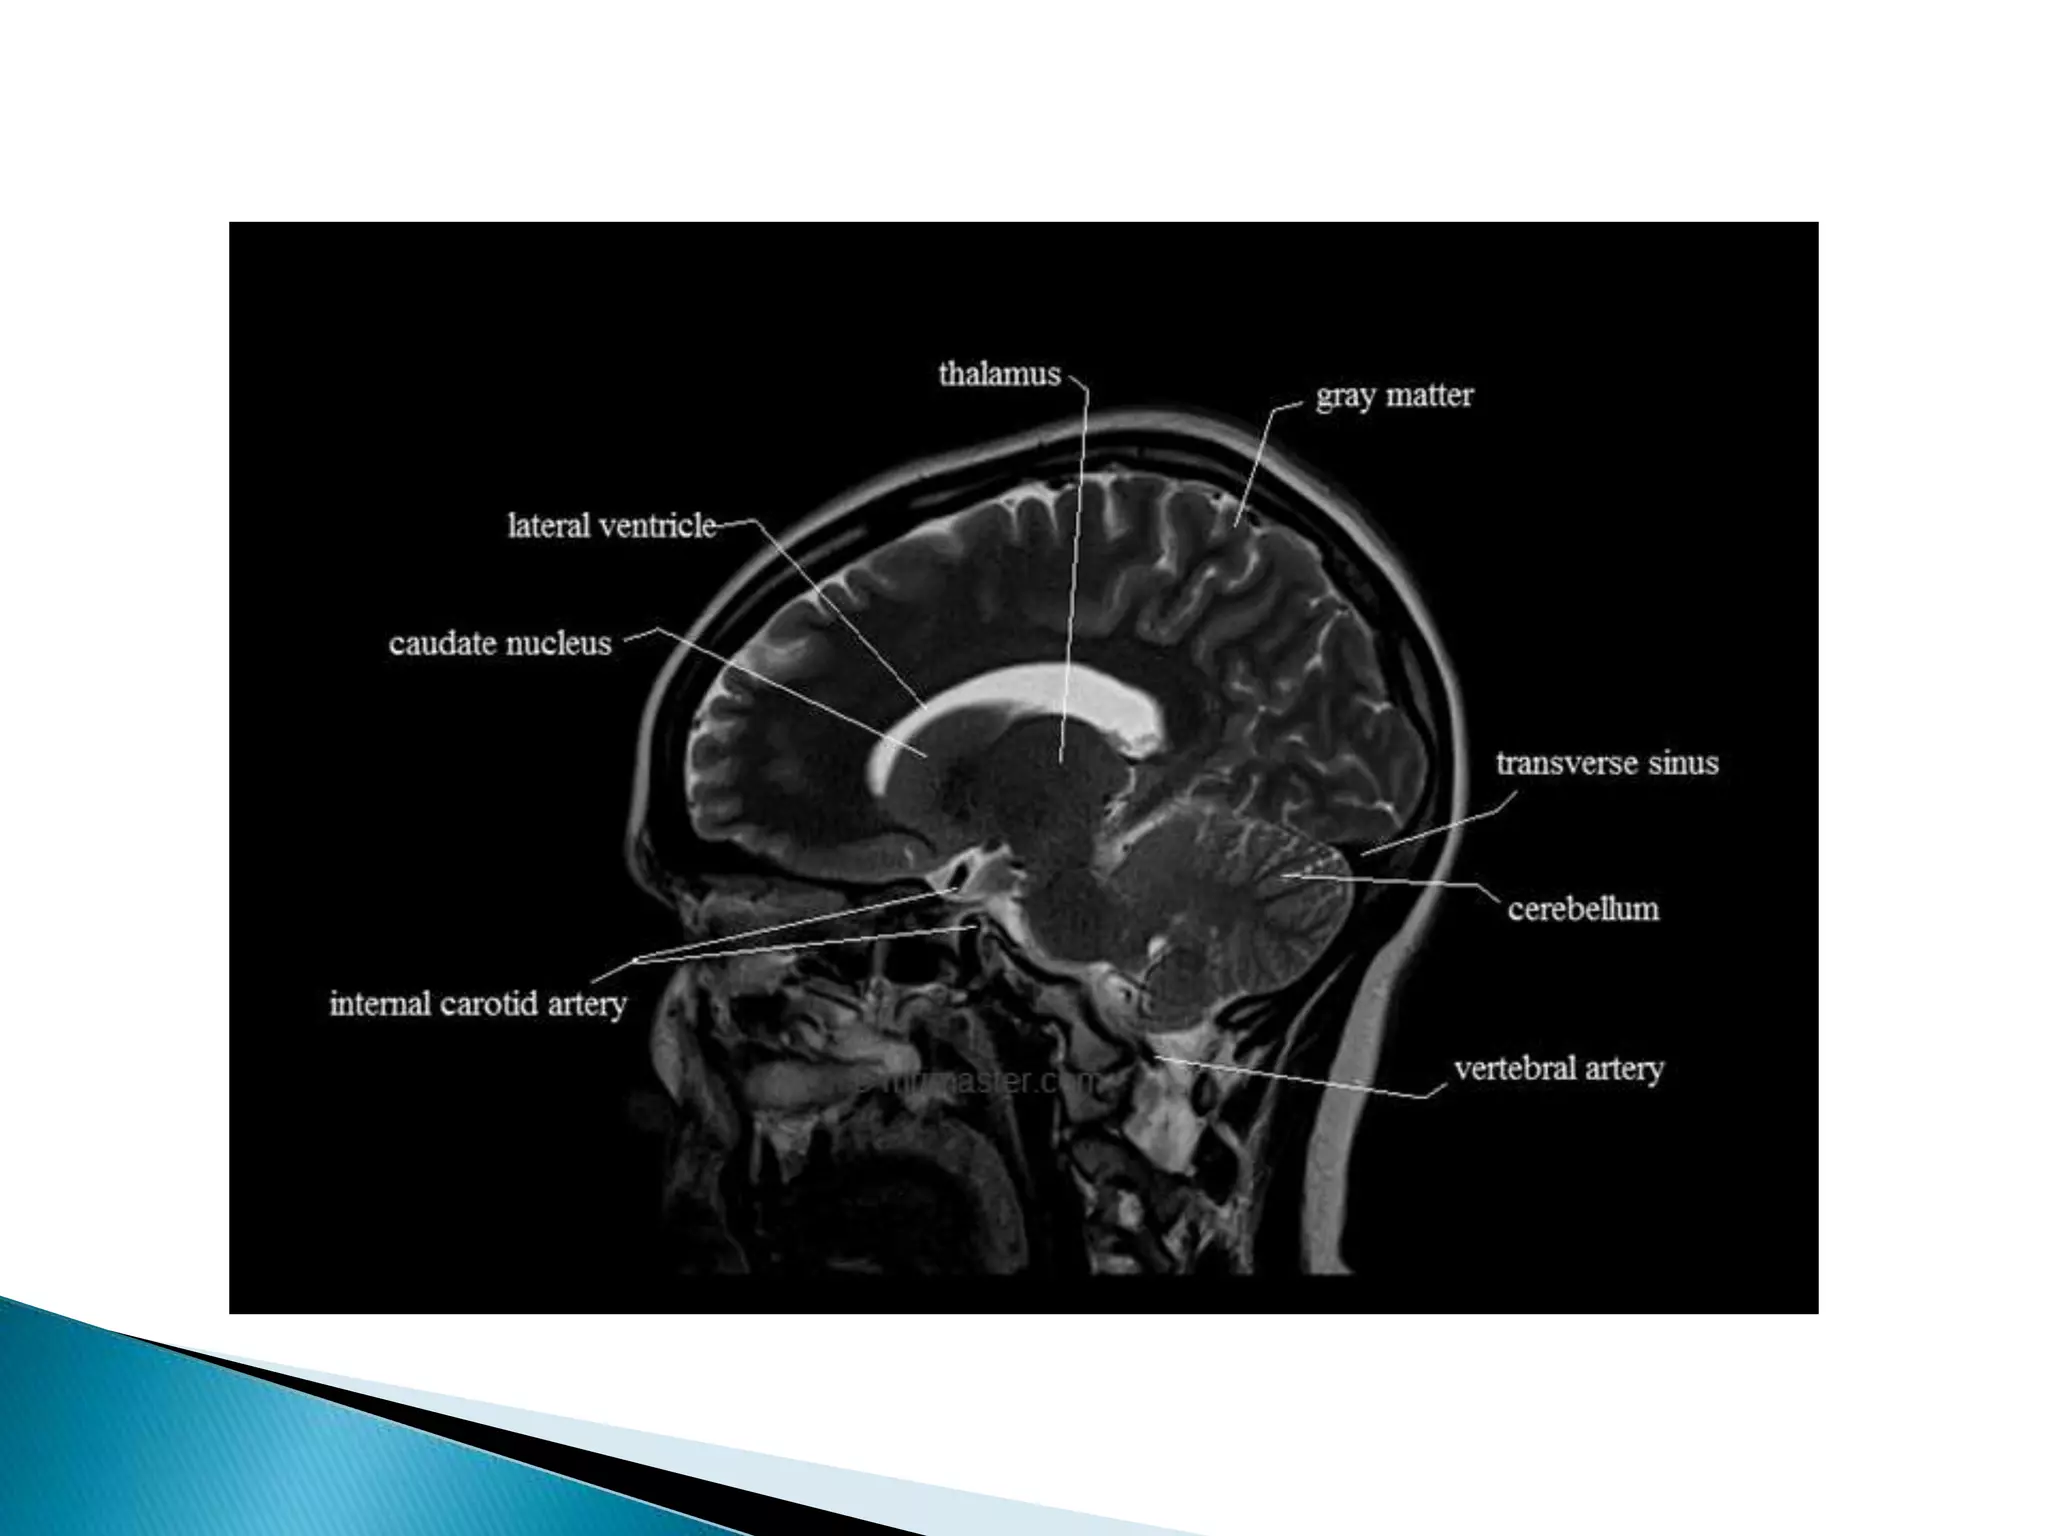

This document lists various medical conditions and provides brief descriptions: A) Abscess, B) Brain infarction and hypoxic insult, C) Crutzfield Jacob disease, D) Diffuse axonal injury and demyelination, E) Encephalitis caused by HSV virus and epidermoid cyst. It also mentions imaging sequences and differential diagnoses for conditions like ischemic stroke and limbic encephalitis.